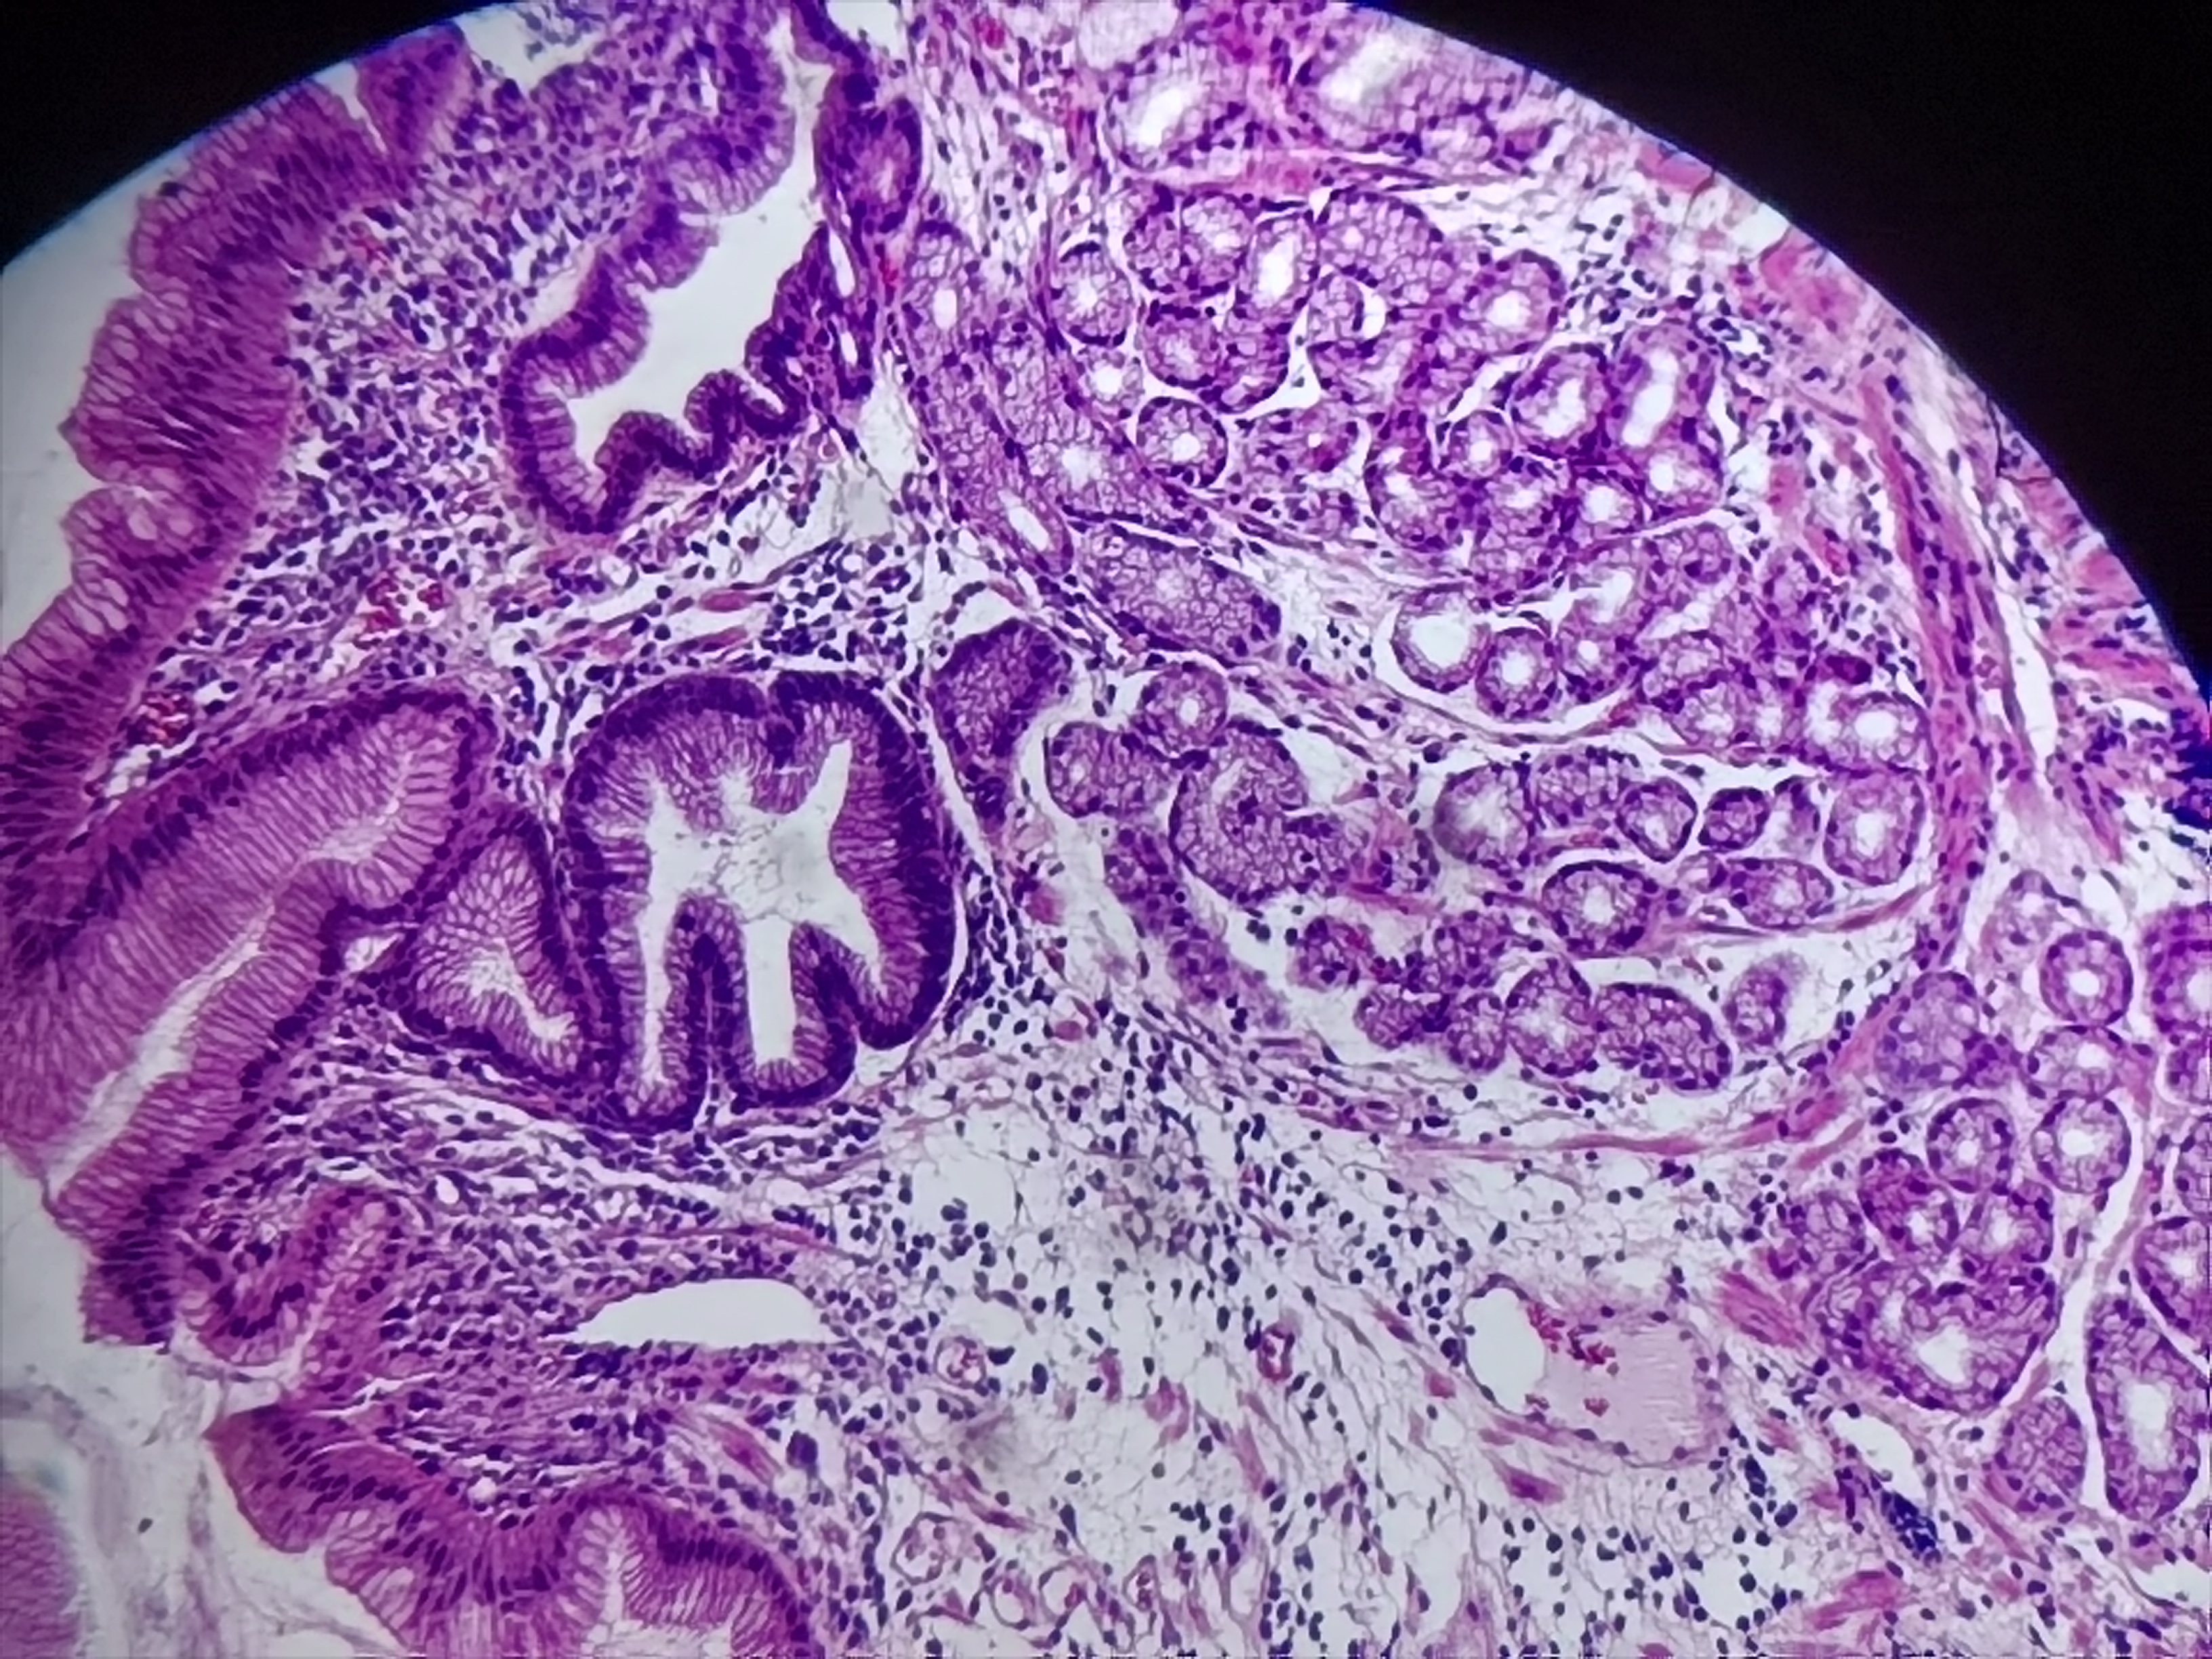

贲门活检

性别

男

年龄

20岁

临床诊断

一般病史

贲门可见糜烂

标本名称

贲门粘膜活检

大体所见

灰白色组织1块

粘膜慢性炎,鳞状上皮增生,固有层淋巴细胞聚集